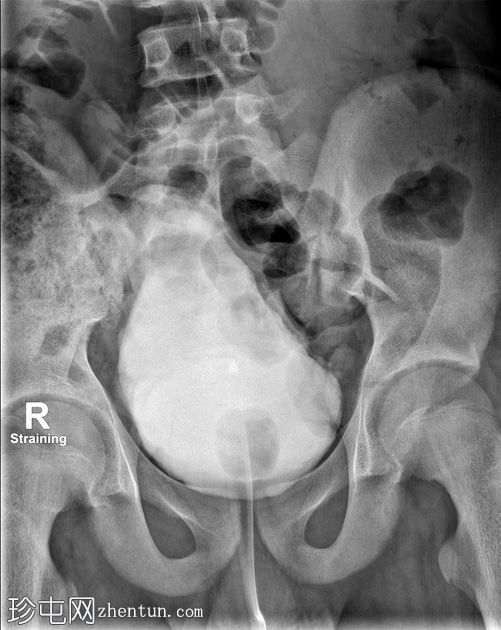

荧光透视

正面

用力

通过导尿管注入造影剂后,可见膀胱延长,膀胱壁不规则,呈小梁状,并有多个大小不一的外囊。

排尿后序列中可见残余尿液。

本病例展示了

神经

源性膀胱的临床和放射学特征。